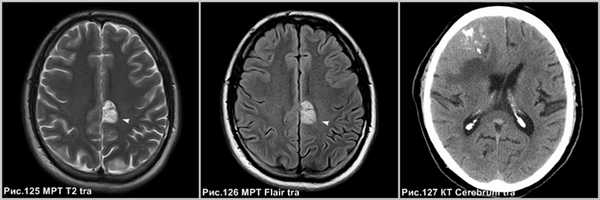

Отличительной особенностью олигодендроглиомы является содержание петрификатов, которое почти никогда не встречается в ПКА, при этом ОДГ почти не накапливает контрастный препарат при в/в усилении.

Олигодендроглиома в лобной доле левого полушария, имеющее повышенный МР-сигнал по Т2 и Flair (головка стрелки на рис.125-126) и содержит петрификаты (стрелки на рис.127).